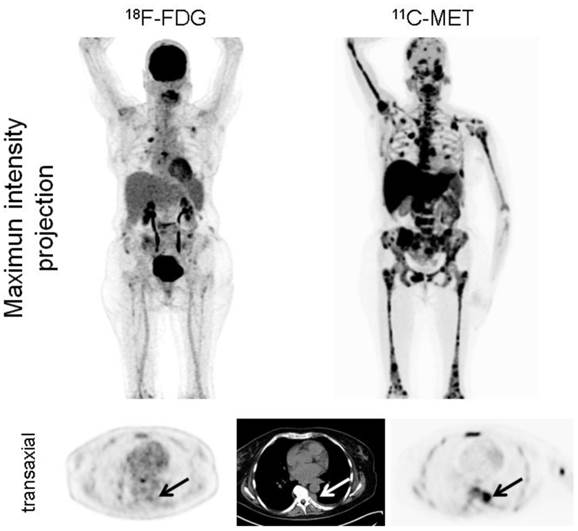

Imaging with MET demonstrated more focal lesions than FDG in 28/43 patients (65.1%, p<0.001). In the remaining patients, an equal number of MM manifestations were detected with both tracers. Most of the lesions exclusively identified by MET located within the bone marrow compartment (28/28; 100%) and in the appendicular skeleton (24/28; 85.7%; figure 2).

Display of a patient (patient #1) with newly diagnosed MM Ig G κ. FDG depicts faint to moderate uptake in the skeleton in contrast to highly intense lesions in MET, e.g. in the right clavicle. Multiple additional intramedullary lesions are clearly detected by MET.

Interestingly, in the 12 patients with EMD, MET detected lesions which were missed by FDG (6/12 subjects; 50%; figure 3). In numbers, FDG detected a total of 28 EMD foci (lymph nodes, n=17; soft tissue, n=9; lungs, n=2), whereas MET depicted 42 lesions in lymph nodes (n=23), soft tissue (n=14), and lungs (n=5). The lesions exclusively visualized by MET were lymphonodal (n=6), soft tissue (n=5) and pulmonary (n=3) manifestations of origin (supplementary table 3).

Display of a patient (patient #6) with MM Ig G κ. FDG depicts moderate uptake in the skeleton in contrast to highly intense lesions in MET (maximum intensity projection, upper row). Additionally, pleural extramedullary disease was exclusively detected by MET (arrows, transaxial slices, lower row). The patient deceased 5 months later.